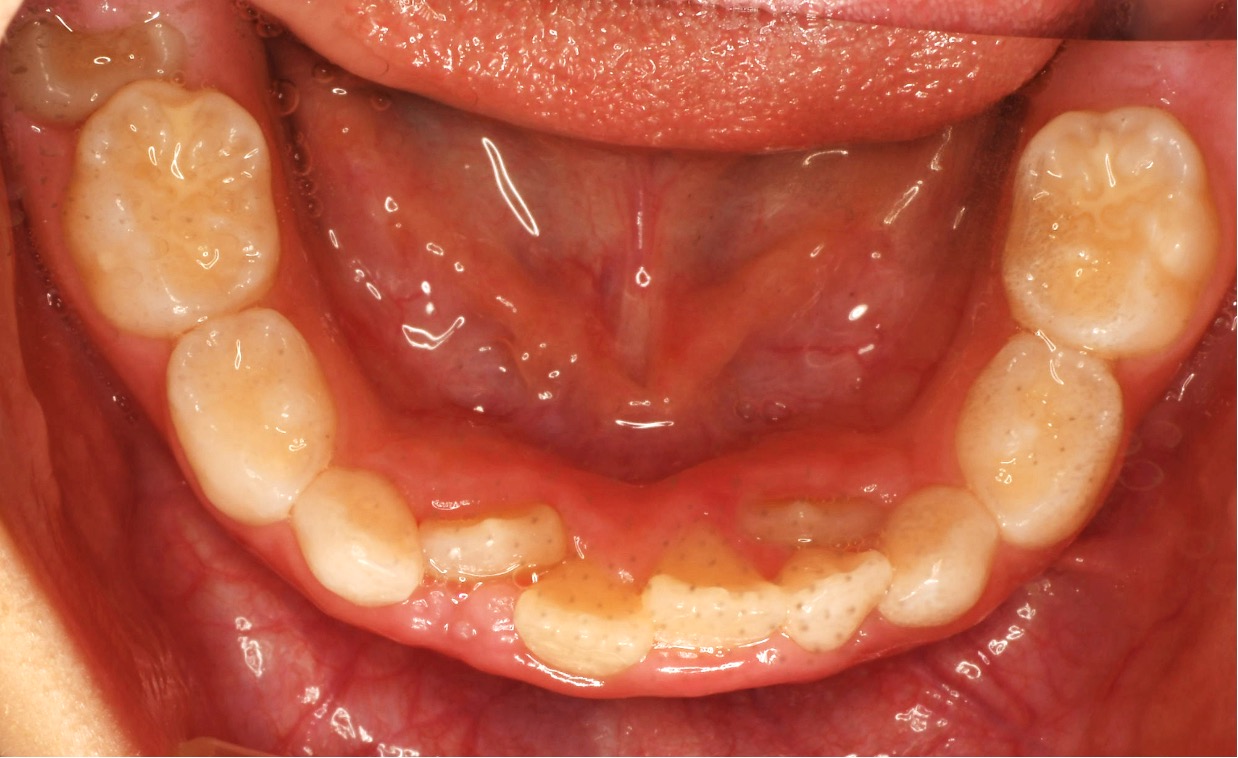

治療後の歯並び

口腔機能訓練をした2年後の8歳。正しい顎の成長。